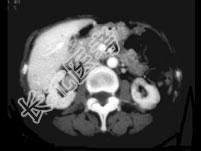

- 单项选择题男,74岁, 间歇性无痛性全程血尿2月余,尿路造影及CT平扫+增强如图所示, 下列说法错误的是 ( )

B、CT平扫示右侧肾盂内软组织块影

C、增强扫描示右侧肾盂内软组织块影轻度强化